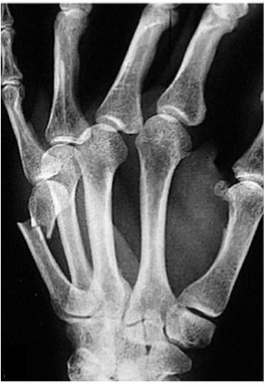

Que fractura se presenta en esta rx

Fractura del cuello del 5to metacariano (del mal boxeador)

Tratamiento de esta fractura

Reduccion cerrada: Maniobra de jazz (compresión en pinza con dedo pulgar, indice y dedo medio haciendo algo de traccion y manteniendo reducción palmar)

Molde de yeso tipo guante

Quirurgico: Placas pequeñas